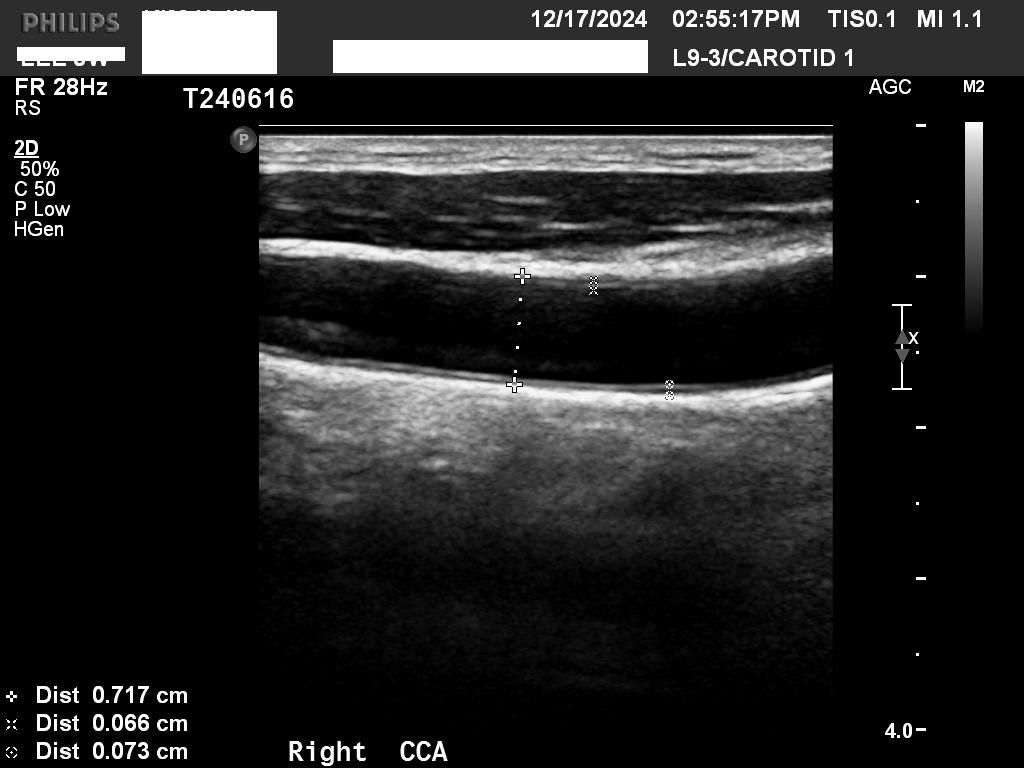

• 4번 째 사진

일반적으로 IMT가 1mm 보다 두꺼운지를 확인하고 혈관에 플라크가 있는지를 봅니다

초음파 사진으로만 보면 동맥경화가 경증으로 있는 것 같습니다